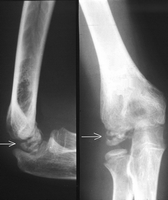

Salter-Harris I Fracture Of The Distal Fibula

Salter-Harris I Fracture of the Distal Fibula tenderness over the growth plate and no tenderness over the ankle ligaments. X-rays may show some swelling or widening of the growth plate, but more commonly the X-rays are normal. ... Return Document

Epiphyseal plate - Wikipedia

The epiphyseal plate (or epiphysial plate, Osteoclasts and osteoblasts from the diaphyseal side break down the calcified cartilage and replace with mineralized bone tissue. A mnemonic for remembering the names of the epiphyseal plate growth zones is "Real People Have Career Options ... Read Article

Growth Plate Injuries - KidsHealth

Causes of Growth Plate Injuries. Most of the time, growth plate injuries happen from falling or twisting. Contact sports, like football or basketball, or fast-moving activities like skiing, skateboarding, sledding, or biking, are common causes. ... Fetch Document